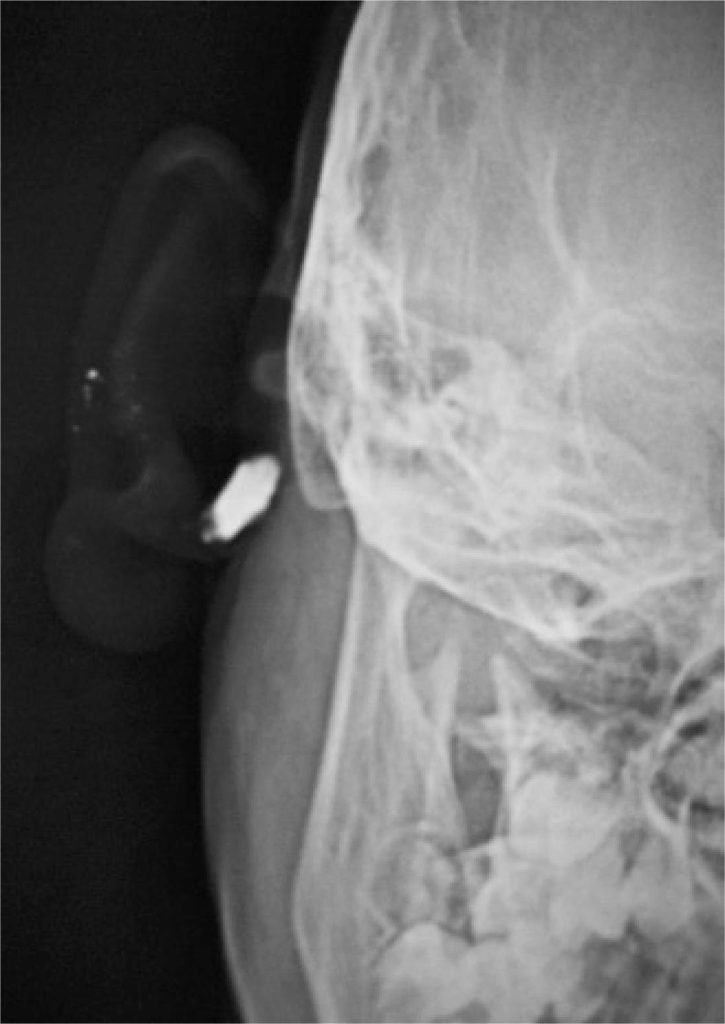

An eight-year-old girl presented with complaints of intermittent discharge from a pit situated in the medial surface of right pinna since early childhood. The discharge was scanty, foul-smelling and mucoid, and occasionally purulent. The frequency had increased in the last year with development of a swelling just below the pit that often got inflamed and caused pain. On examination, an opening was noted just above the lobule leading to a swelling that reached the post-auricular sulcus (). An area of scarring and pigmentation in the lateral surface of the pinna in immediate vicinity to the external auditory canal (EAC) − reminiscent of past inflammations involving the EAC skin, could be seen that corresponded to the sinus tract (). Also, similar pits, which were asymptomatic were noted on the ascending helix of the right () as well as left pinna (). After controlling the infection with antibiotics, a sinogram was ordered to assess the post-auricular lesion, which showed a sinus tract that ballooned in to the soft tissue of the neck, just below the mastoid process and EAC, and posterior to the ramus of the mandible (). The tract was excised under general anesthesia. Peroperatively, it was found to end blindly stopping just short of invading the parotid tissue.